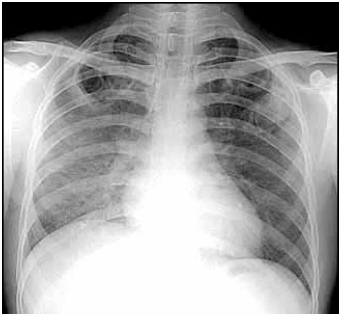

Com base na radiografia abaixo, assinale a alternativa correta: